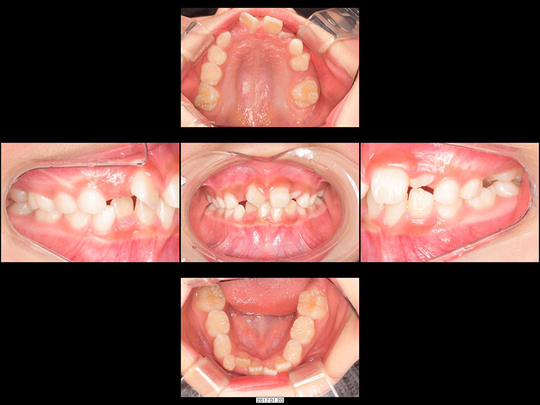

Sさん 初診時9歳 女性

矯正前

矯正治療中

矯正後

治療の説明

上の前歯2本が生えてこないのを心配しておられたのに、「様子見しましょう」とずっと言われ続けてお困りでした。中には「大学病院でしか対応できません」と言われたこともあったようです。

CT検査の結果、歯が歯ぐきの中に埋まった埋伏(まいふく)といわれる状態でした。歯ぐきだけでなくあごの骨まで歯に被さっていたため、埋伏している前歯の表面を傷つけずにあごの骨まで削り、引っ張り出すための外科処置(外科的開窓牽引による矯正)を行いました。奥歯の乳歯から永久歯への生え変わりのスペースもないので、あわせてあごの骨も拡大しています。

治療の期間・回数

40か月、40回

​費用

541,000円

リスクや副作用:出血を伴う可能性があります。治療後に、痛みや腫れ、出血を引き起こす可能性があります。

装置に慣れるまでに1週間ほどかかる可能性があります。歯列を広げる過程で少し痛みを感じる可能性があります。装着時に多少しゃべりづらくなる可能性があります(2~3週間ほどで慣れます)。